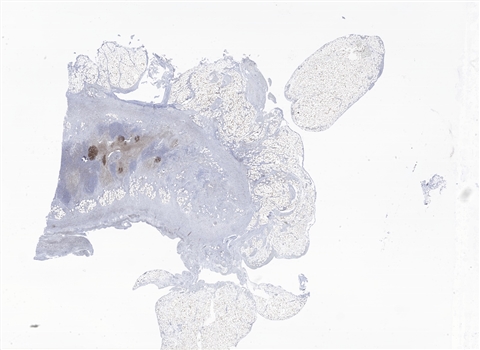

案例7 (6972)

性别:       年龄:43

患者详情: 半月前,无明显诱因出现头晕,无恶心呕吐,无发热乏力等不适,CT显示胃体部腔内见一直径约2.06cm结节影,增强扫描不均匀强化,影符合间质瘤表现,请结合组织学检查。电子胃镜示:胃体溃疡性肿物并出血,胃窦溃疡。胃体肿物考虑间质瘤可能。

医院: 南昌大学第二附属医院